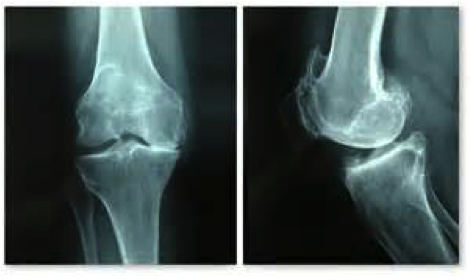

Quels sont les examens complémentaires nécessaires ?

Les examens complémentaires vont confirmer le diagnostic, et faire le bilan de lésions associées (ménisques, lésions ligamentaires) :

- Bilan d’imagerie : IRM, Arthroscanner.

Risque à long terme

C’est en effet le risque d’arthrose. La répétition des accidents d’instabilité, surtout si les ménisques, véritables amortisseurs, sont également déchirés, peut entraîner cette usure du cartilage du fémur et du tibia qui représente l’arthrose du genou.

Elle peut devenir responsable de douleurs persistantes, et d’épanchements à répétition.

Le traitement d’une telle arthrose peut être difficile en raison de sa survenue chez des sujets souvent encore jeunes…